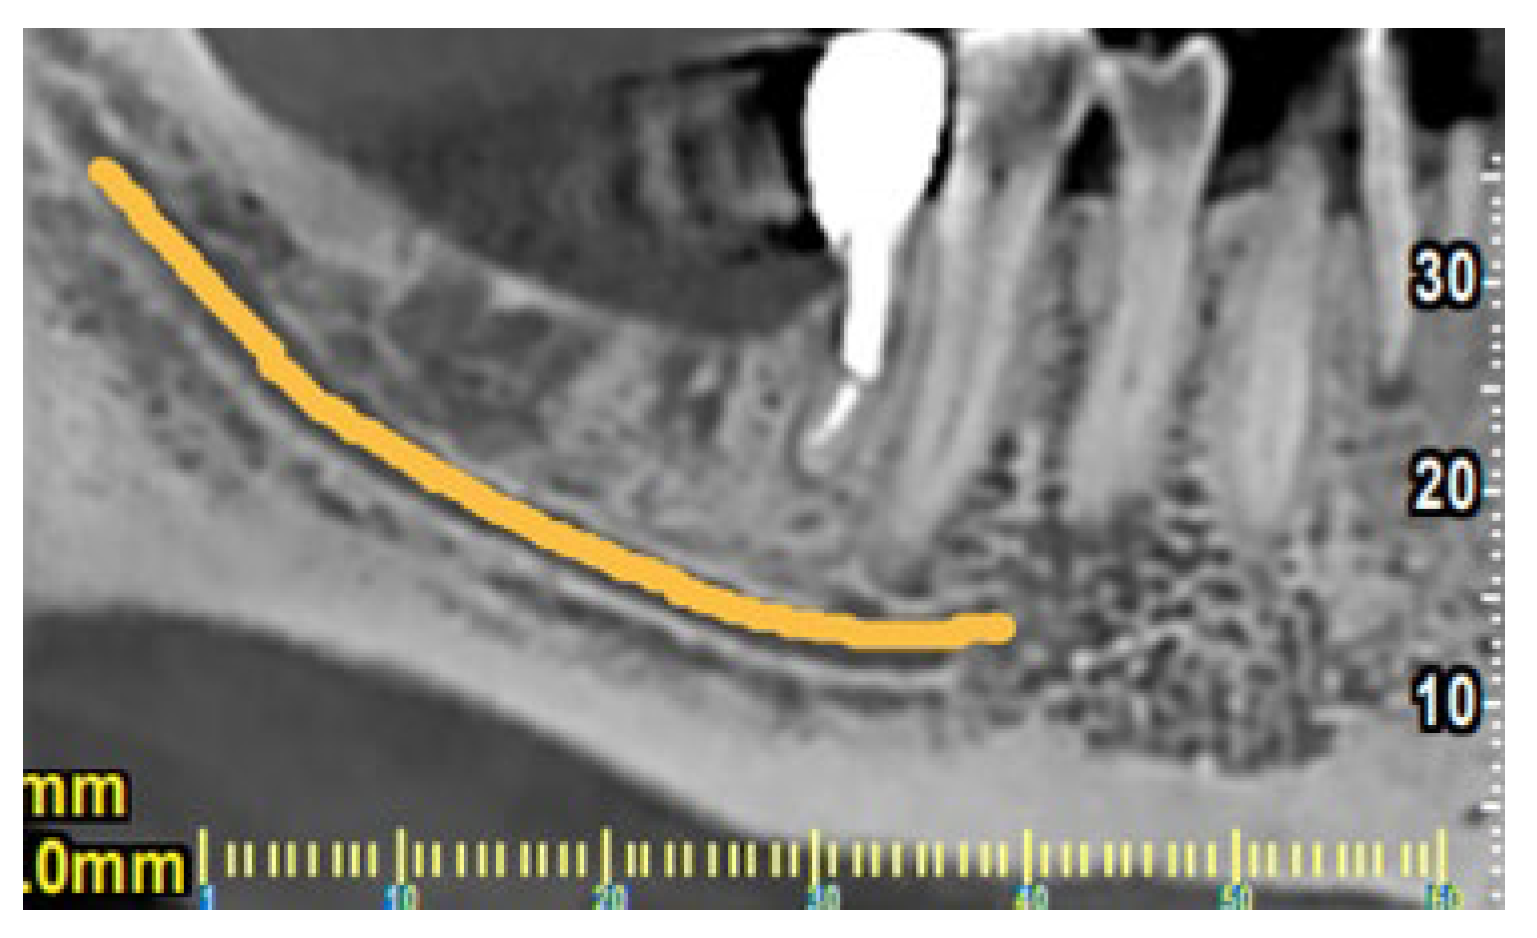

The clinical examination in this area revealed that the gingiva in the molar region was moderately inflamed, percussion of the molars elicited a slight sensitive reaction on tooth #37 and no mobility was present. However, a deep narrow pocket (16mm) in the buccal aspect of the mesial root of the second molar (#37) was found upon probing. A periapical radiograph in this area showed a J- shaped radiolucent area in the mesial root of the #37 tooth extending from crest of the alveolar ridge to the apex of the tooth (Figure 3). Based on these clinical and radiographic findings a CBCT examination of the lower jaw was suggested to evaluate firstly if there is a vertical fracture on mesial root of tooth #37 and secondly to verify the consistency and dimensions of the bone for implant placement in the region of #46-#47. (Figure 4 and Figure 5). From the CBCT evaluation the suspected vertical root fracture in the mesial root and the suitability for implant placement were confirmed [34] (Figure 4).

Figure 4. CBCT section of tooth #37 illustrating the pattern of bone resorption alongside the mesial root.